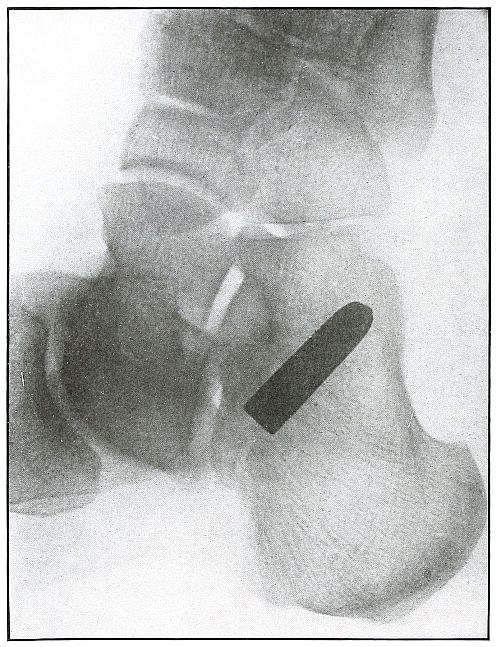

Plate 7.

_

[Pg 25]

Rifle—Plate 7.

SPINAL REGION.

Gunshot Wound of the Spinal Region, with Lodgment of the Missile.

The bullet was either dum-dummed or unjacketed because its soft nose mushroomed, striking the crest of the ilium, penetrated the lumbar muscles, and struck the side body of the third lumbar vertebra without producing fracture.

The exposure, as the spinous processes show, was made with the spine next to the plate, and the slight shadow, somewhat larger than the projectile—to judge the size from the undeformed diameter—shows it to be anterior to the vertebra. The shadow is deep enough to indicate the location fairly near to the plate, and, almost certainly, not in the abdominal cavity, where the distance from the plate would have made the shadow less dense and the movement of respiration probably would have given it a blurred outline. The shadow of the localizing cross gives a standard of density to be compared with the shadow of the projectile in making the estimation.

The treatment is conservative; only pain, paralysis, impaired function, or sepsis indicate interference. [Pg 26]